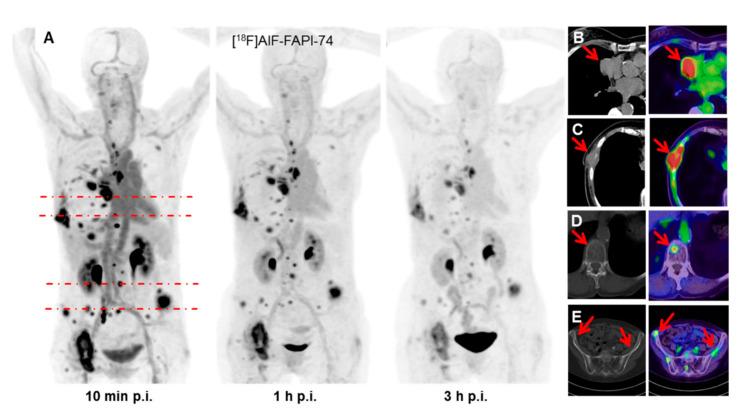

Small molecules targeting fibroblast activation protein (FAP) have emerged as a new group of tracers for positron emission tomography (PET) in 2018. The purpose of this systematic review is therefore to summarize the evidence that has been gathered to date in patients and to discuss its possible implications for radiotherapy planning. The MEDLINE database was searched for the use of FAP-specific PET in cancer patients and the records were screened according to PRISMA guidelines. Nineteen studies were included. While dedicated analyses of FAP-specific PET for radiotherapy planning were available for glioblastoma, head and neck cancers, lung cancer, and tumors of the lower gastrointestinal tract, there is still very limited data for several epidemiologically significant cancers. In conclusion, FAP-specific PET represents a promising imaging modality for radiotherapy planning that warrants further research.

2018年,靶向成纤维细胞活化蛋白(FAP)的小分子已成为正电子发射断层扫描(PET)的一类新型示踪剂。因此,本系统评价的目的是总结迄今为止在患者中收集到的证据,并讨论其对放射治疗计划的潜在影响。检索MEDLINE数据库中FAP特异性PET在癌症患者中的应用情况,并根据PRISMA指南筛选记录。纳入了19项研究。虽然已有针对胶质母细胞瘤、头颈癌、肺癌和下消化道肿瘤的FAP特异性PET用于放射治疗计划的专门分析,但对于几种具有重要流行病学意义的癌症,数据仍然非常有限。总之,FAP特异性PET是一种很有前景的用于放射治疗计划的成像方式,值得进一步研究。